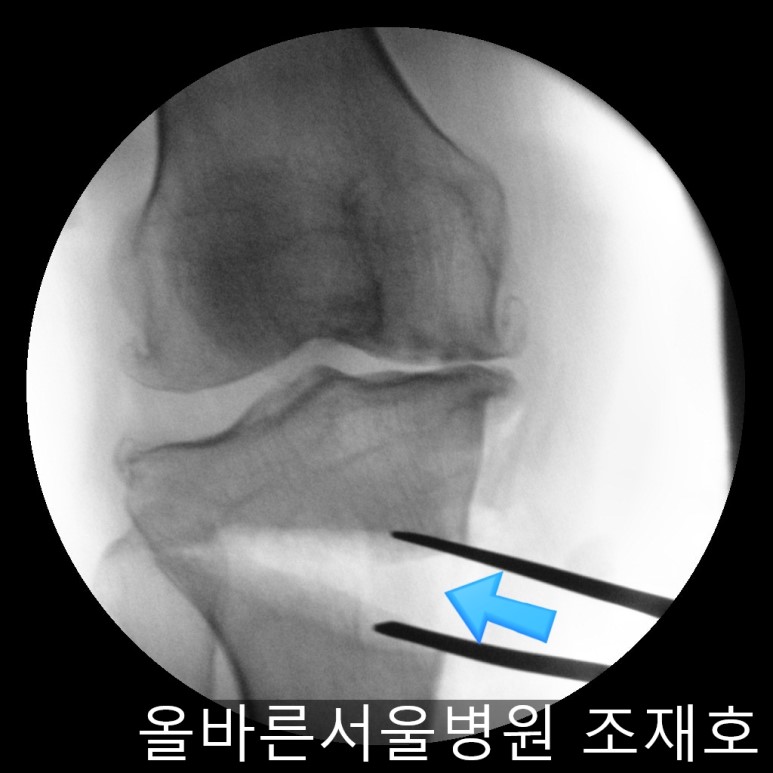

确保正面准确矫正。

侧位影响中也没有slop增加,矫正成功。

手术后可通过片子看到矫正后的正面样子。

此时内侧稍微分开,开始行走且软骨开始再生,内侧会更加分开。

侧面也矫正成功。